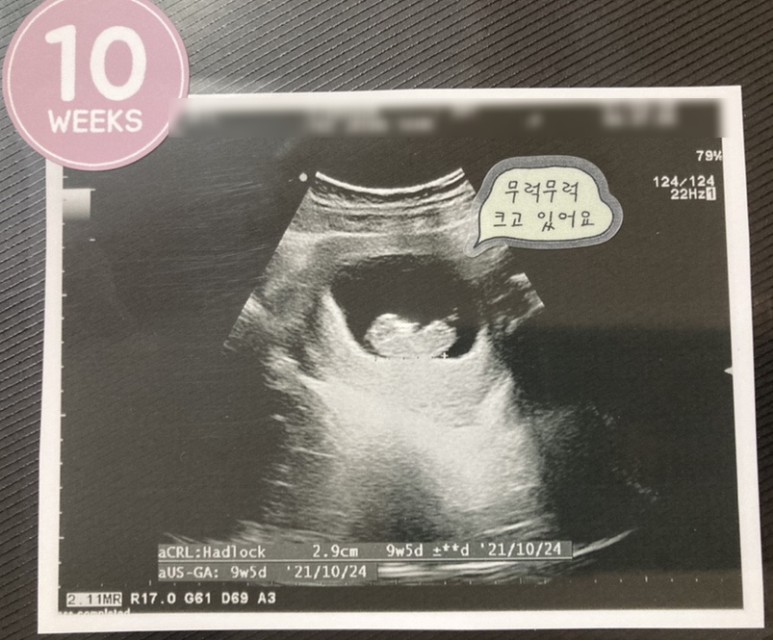

10w0d :: 2.9cm 예정일이 또 조금 밀렸네 그러나 크게 걱정할 일은 아니라고 한다.입덧은 나아졌지만 완전히 사라진건 아닌 애매한 컨디션!! 퇴근해서 집에 오면 시작된다.그래도 10주차가 되면서 식사량도 조금씩 늘었고 점심에 직원들과 맛있는 것도 먹으면서 하루 한끼는 맛있는 것도 먹고 잘 버틸 수 있었다.9주차에 입덧이 줄어든 뒤부터 복통이 심해졌지만 10주차에 그것도 적응했는지 가끔 따끔거리는 것 외에는 신경 쓰이지 않았다.+ 초음파 – 진료비 35,300원 11주차. 조금씩 줄어들고 있는 입덧과 복통 증세